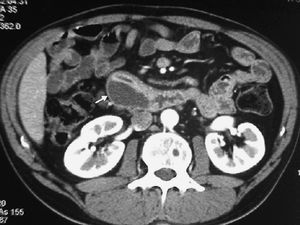

El duodeno también puede verse afectado tanto por extensión de tumores vecinos, siendo los más frecuentes los de estómago, como por neoplasias de colon transverso, páncreas (fig. 21), vesícula, hígado y riñón derecho1,2 (fig. 22).

Fig. 21--Neoplasia de páncreas. (A) Corte transversal de ecografía en el que se aprecia masa pancreática (P) que infiltra la pared duodenal (D). (B) Tomografía computarizada con contraste intravenoso correspondiente, donde se puede observar dilatación gástrica por la obstrucción.